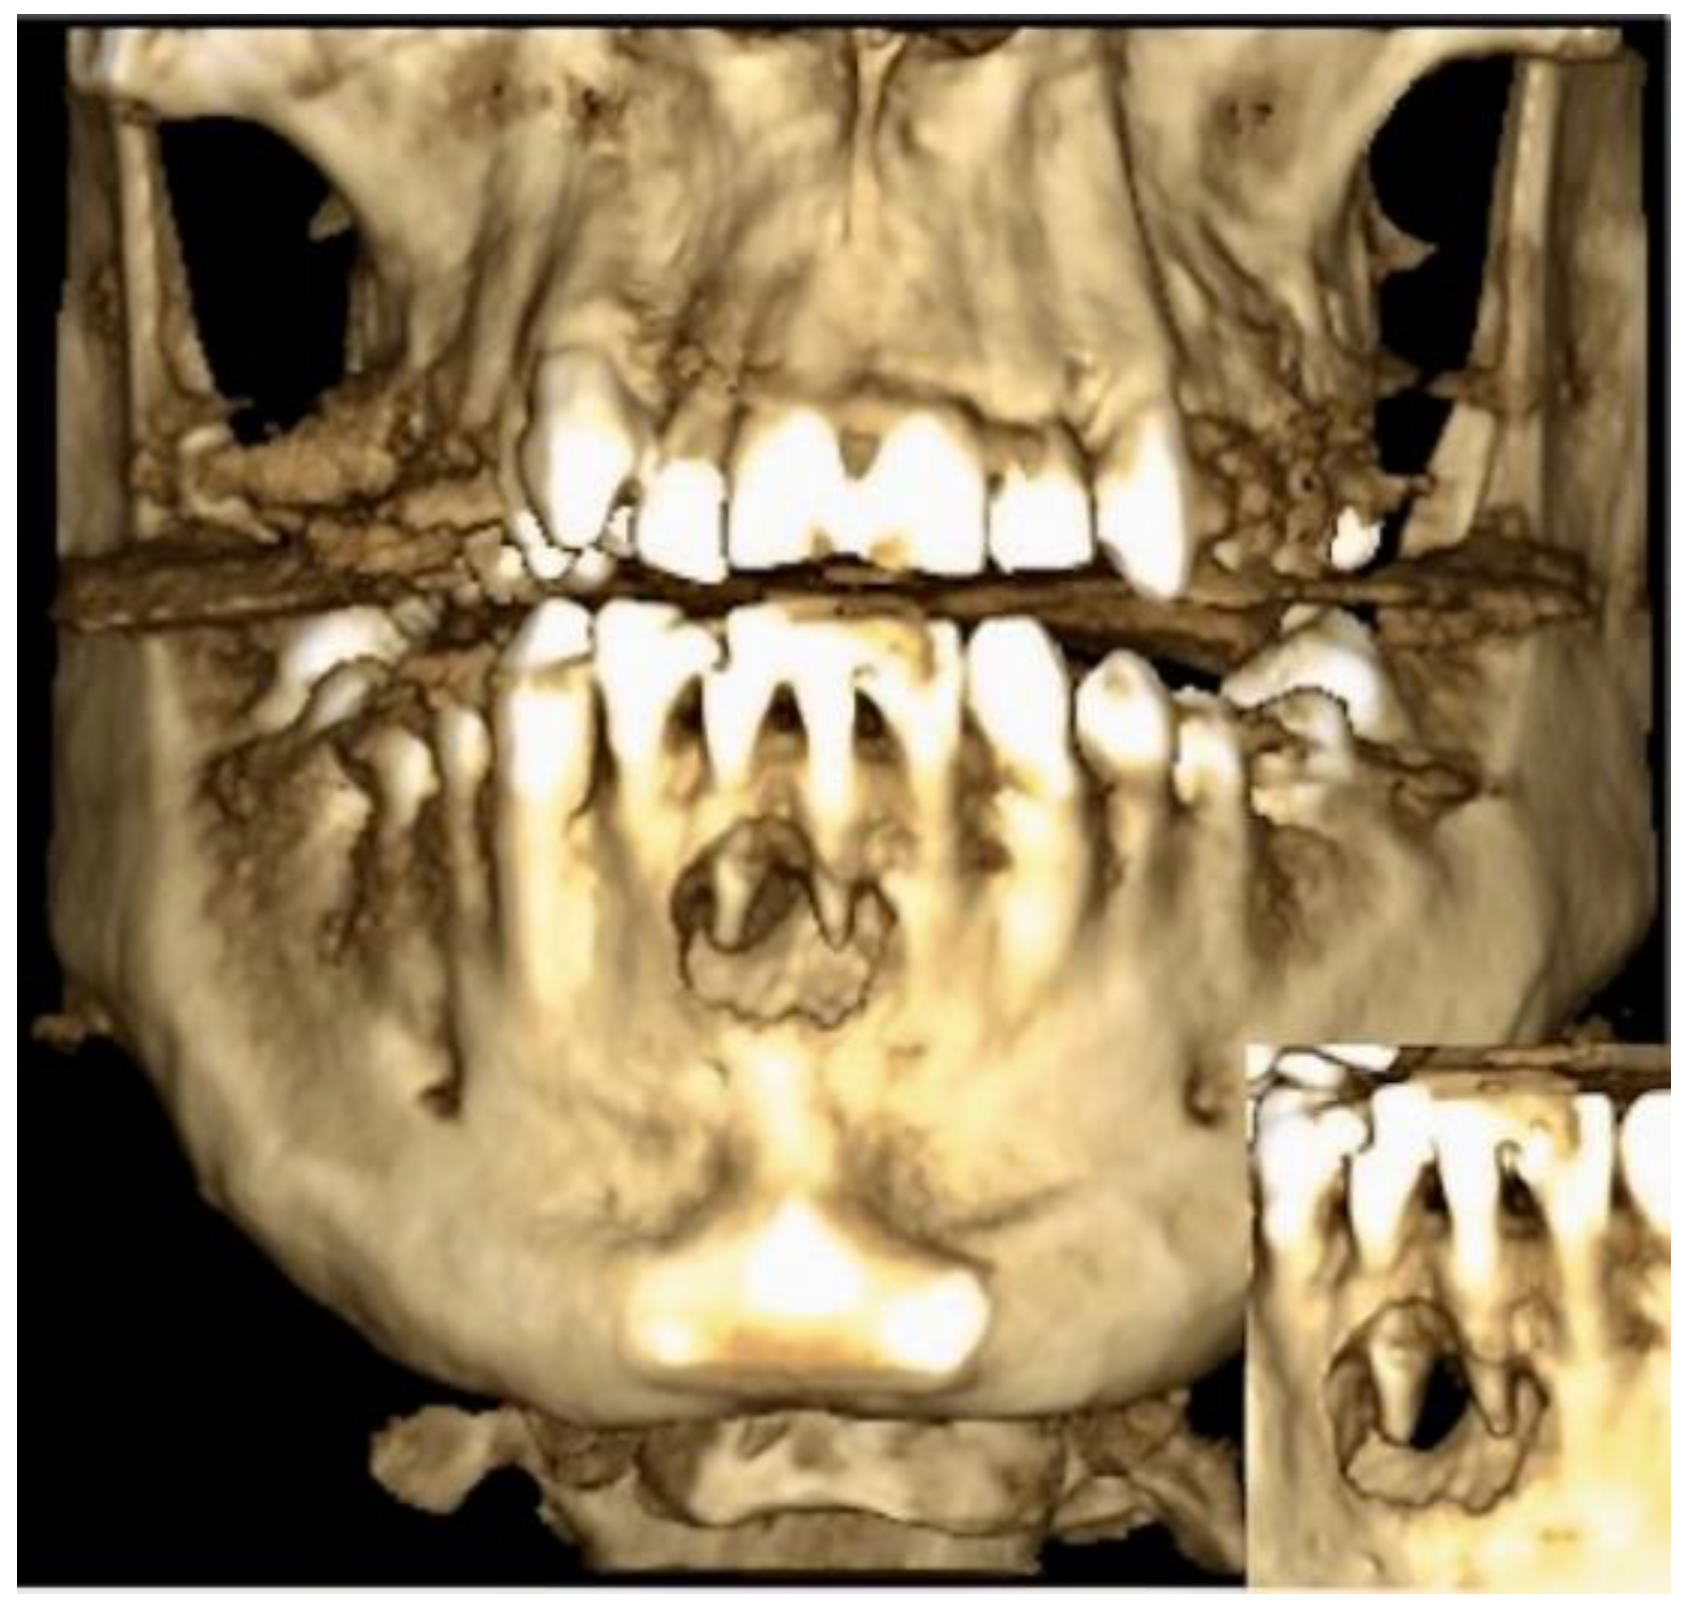

2. Case Description